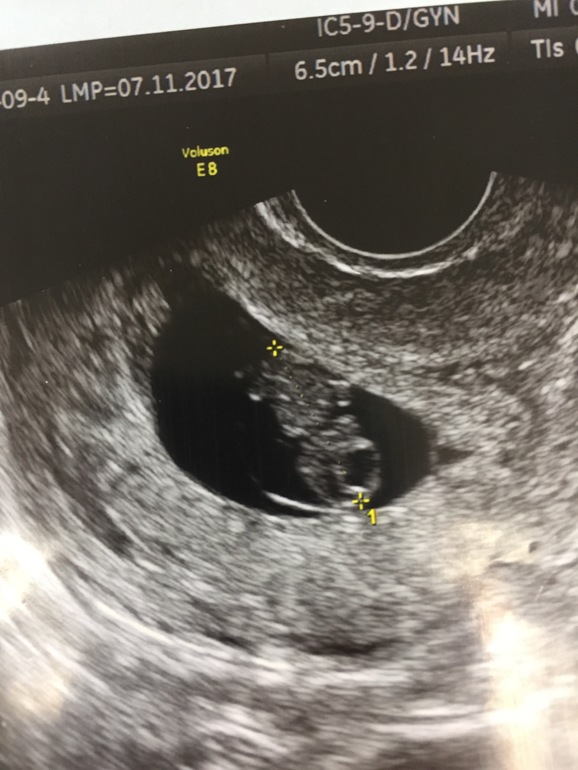

Утром писала что боюсь зб и т.п. Вот теперь полное спокойствие)ни каких угроз, все хорошо))знакомьтесь)вот и мы)уже 2 см почти)и очень буйные как сказал доктор) 8 недель 4 дня)